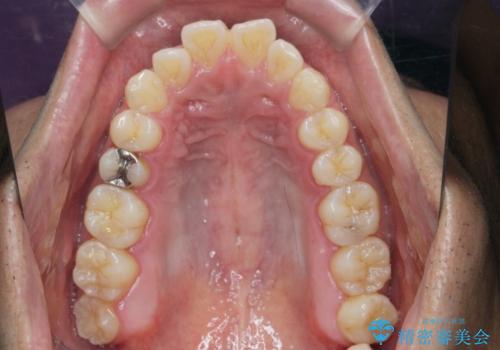

- 前歯のガタつきをきれいにしたい、と矯正治療を希望され来院されました。

マウスピース矯正インビザラインを用いてガタつきをきれいに並べていきます。

外側に傾斜していた前歯の角度も良くなり、「前歯の見た目が良くなった。」、と喜んでいただくことができました。